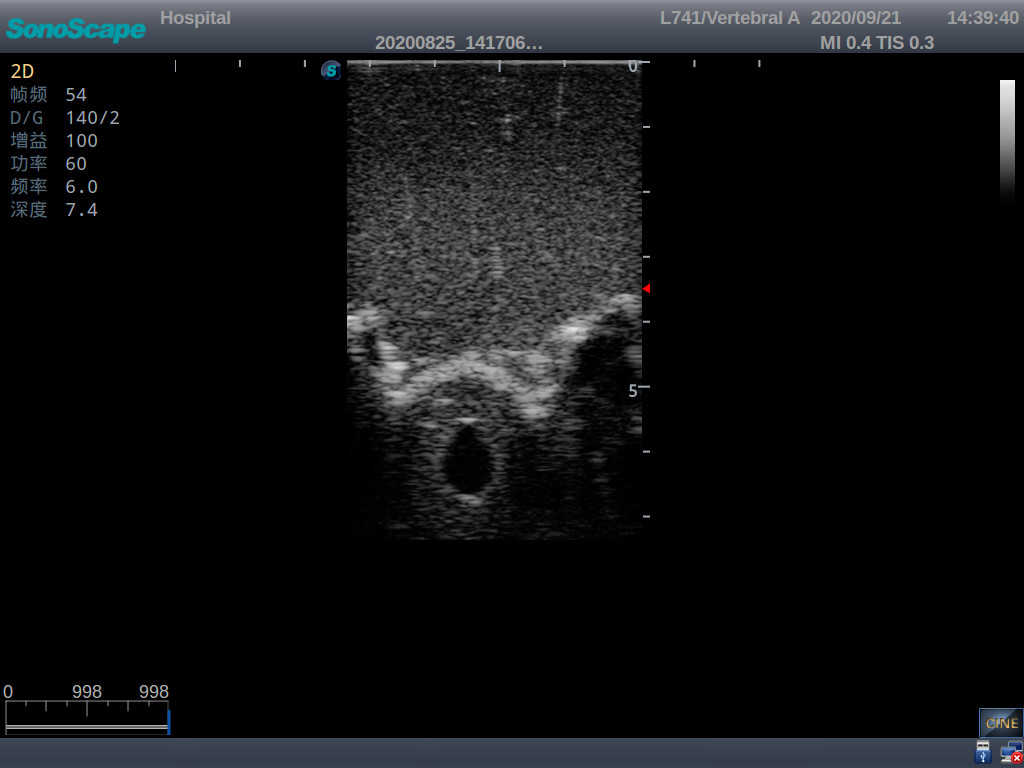

Adult Lumbar Puncture Ultrasound Training Model

This model is an ideal choice for ultrasound-guided adult lumbar puncture training with true-to-life skin feel and touch, accurate anatomical structures as well as real clinical ultrasound images. Realistic resistance to needle tips and correct landmarks provide excellent hands-on experience.

Accurate anatomical structure of L1-L5 and the vertebral canal

2)  Real clinical ultrasound images

1)   Ultrasound-guided lumbar puncture practice